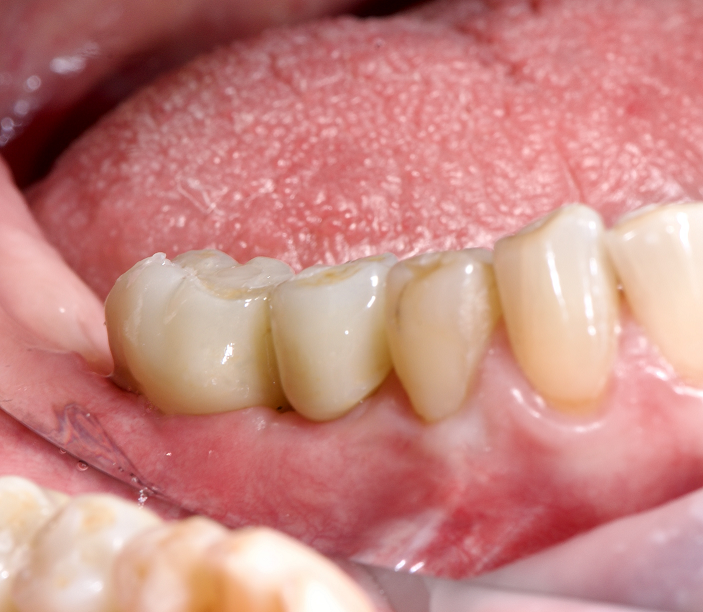

Восстановление утраченного зуба 45 у возрастной пациентки.

✔️ В мягкую кость области зуба 45, удалённого незадолго до обращения, установлен агрессивный корневидный имплант Vega+

✔️ Через 4 месяца проведено протезирование керамической коронкой с трансокклюзионной фиксацией.

Для просмотра описания этапов лечения кликните по фото